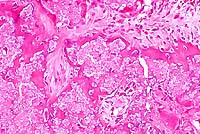

- Microscopic examination revealed a tumor-like mesenchymal

proliferation consisting of chondrocytes forming a rim of hyaline

cartilage surrounding spongy bone. The cortex of each growth

was irregular, and the spongy bone had trabeculae supporting

fatty marrow. Remnants of cartilage persisted in the osseous

mass. The histological picture suggests a peripheral chondromatous

proliferation followed by imperfect central endochondral ossification.

4x

obj

- Case 20-2. Bone. Irregular endochondral bone formation

occuring deep within cancellous bone. Dark cells in the lower

right are osteoclasts.